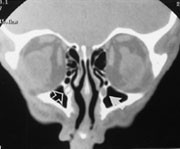

Ved mistanke om retinoblastom utføres først oftalmoskopi og ultralydundersøkelse. Hvis ultralydundersøkelsen ikke viser kalk, bør CT gjøres (fig 3). Hvis ultralydundersøkelse eller CT viser kalk, bør MR utføres for å avgjøre om det er ekstraokulær utbredelse av tumor (fig 4), samt vise dette i forhold til n. opticus og orbita (5). Ved bilaterale eller familiære retinoblastomer er MR indisert for å utelukke eller påvise asymptomatisk midtlinjemalignitet, såkalt pinealoblastom (6).